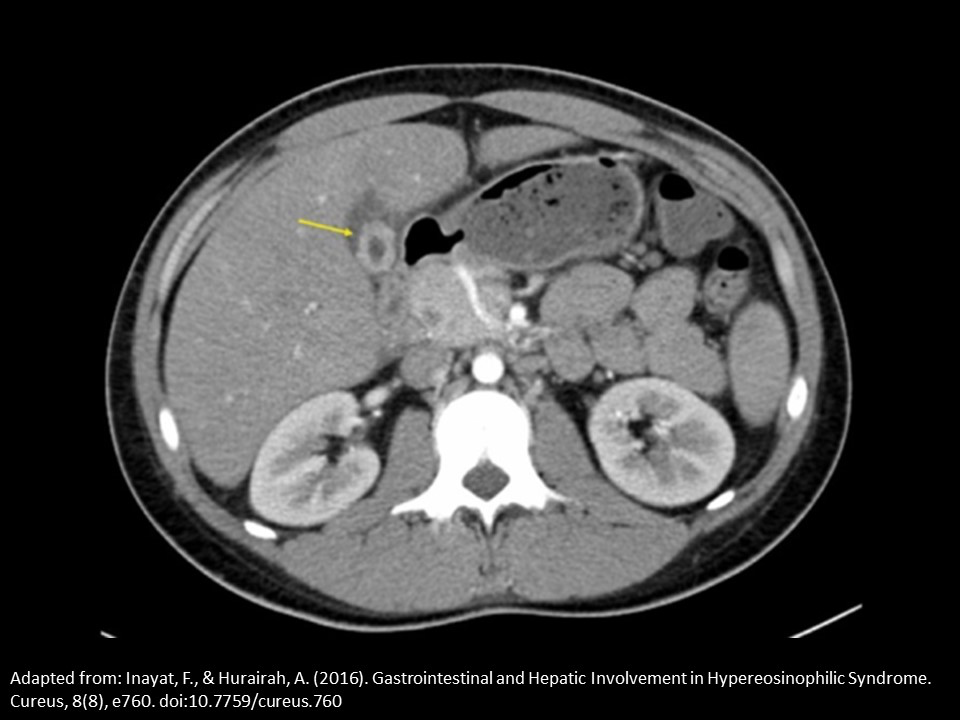

A patient is referred for an abdominal ultrasound due to an abnormal CT scan. The yellow arrow indicates the gallbladder. Based on the single CT image, which of the following is expected finding on the ultrasound evaluation.

gallbladder wall thickness >3 mm